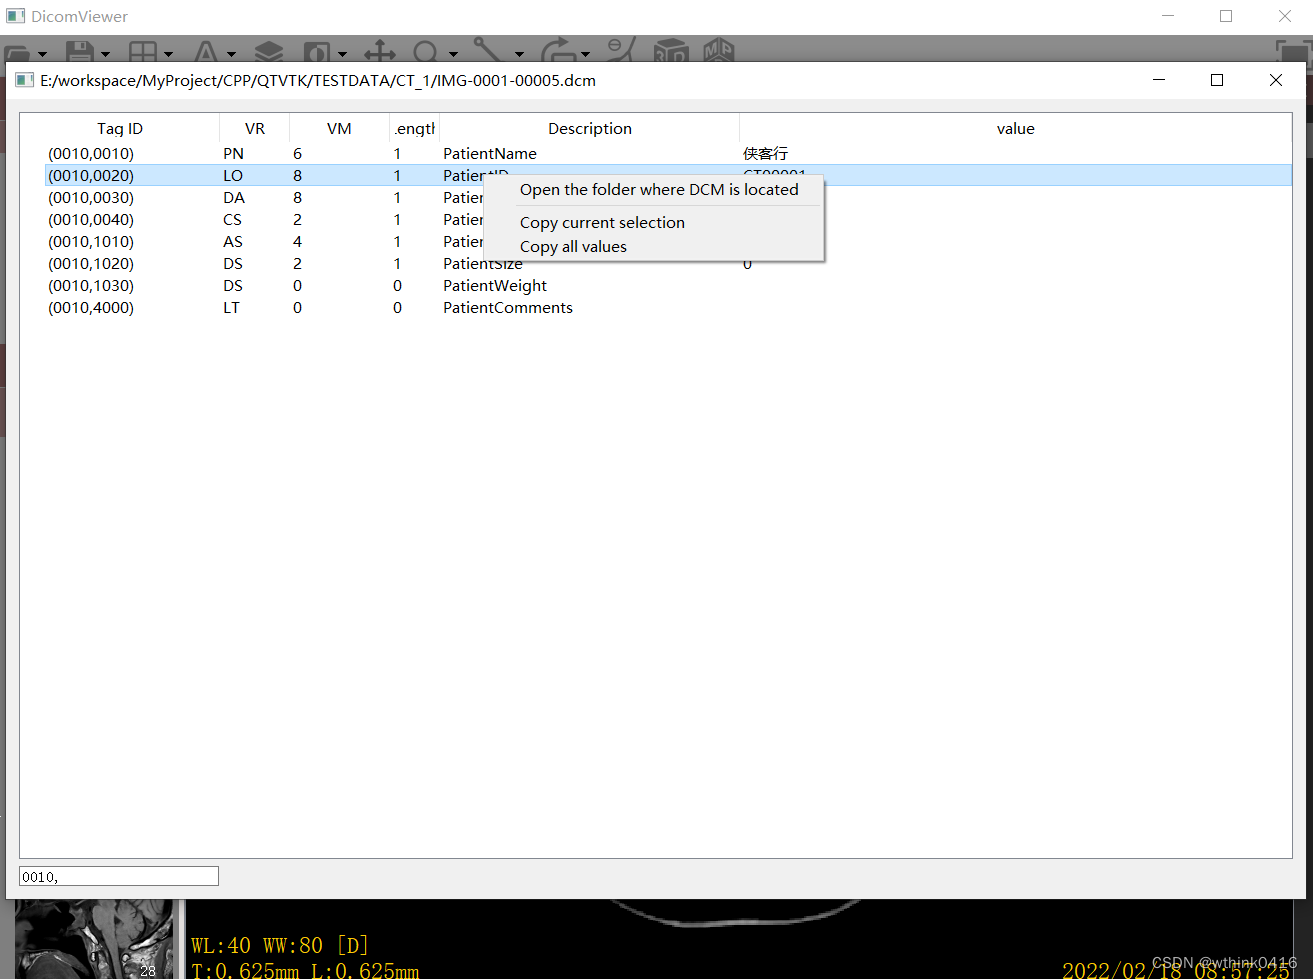

3、点击工具栏中A图标,可以实现隐藏和显示四角信息,同时下拉菜单包含显示该图像的所有Tag值,以及隐藏患者信息等功能,Tag值显示界面左下角可根据输入进行筛选。